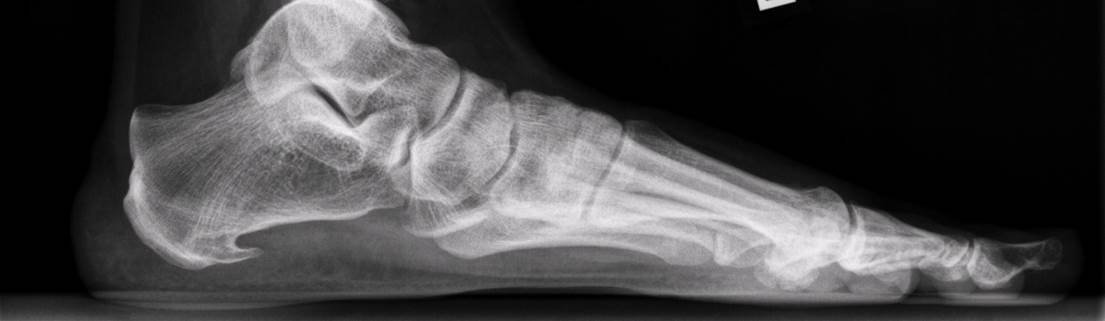

Een hielspoor is een verkalking aan de onderkant van het hielbot (calcaneus). Deze zit bij de aanhechting van de peesplaat die naar de voorvoet loopt. Een hielspoor is waarneembaar op röntgenfoto, maar ook is hij goed te zien op een echo.